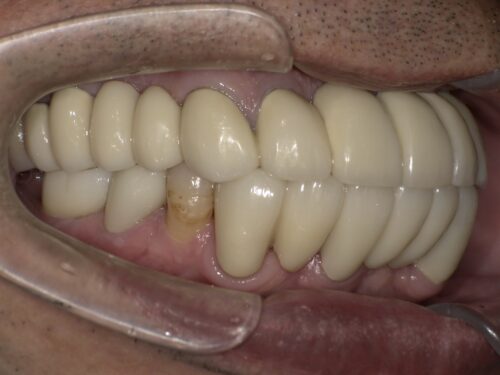

下の奥歯はインプラントを入れることで噛める範囲を増やしています。

お口の全体を使って噛むことは、

一部の歯に負担がかかることを防ぎ、

歯を長持ちさせることにつながります。